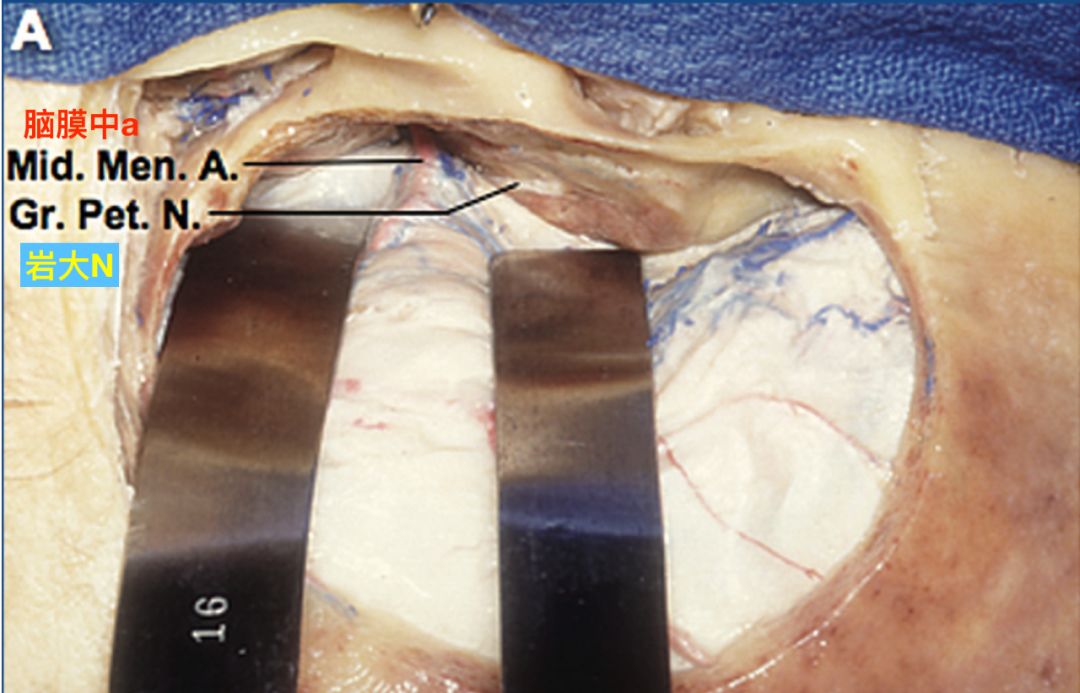

右侧颞部开颅,显露中颅窝底的脑膜中动脉和岩大神经(El-Khouly 2008)。

抬起中颅窝底的硬脑膜,显露岩动脉自脑膜中动脉的发出点。岩动脉在其起点远端进入中颅窝底的骨质(黄箭)(El-Khouly 2008)。